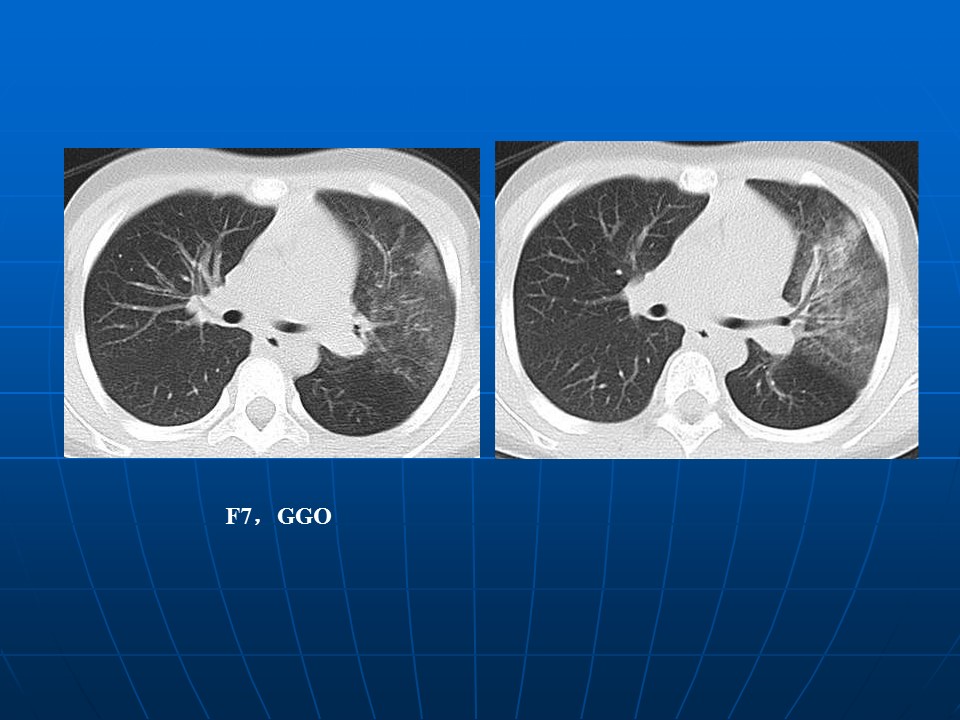

如何在影像上判断新冠病毒肺部感染是否好转